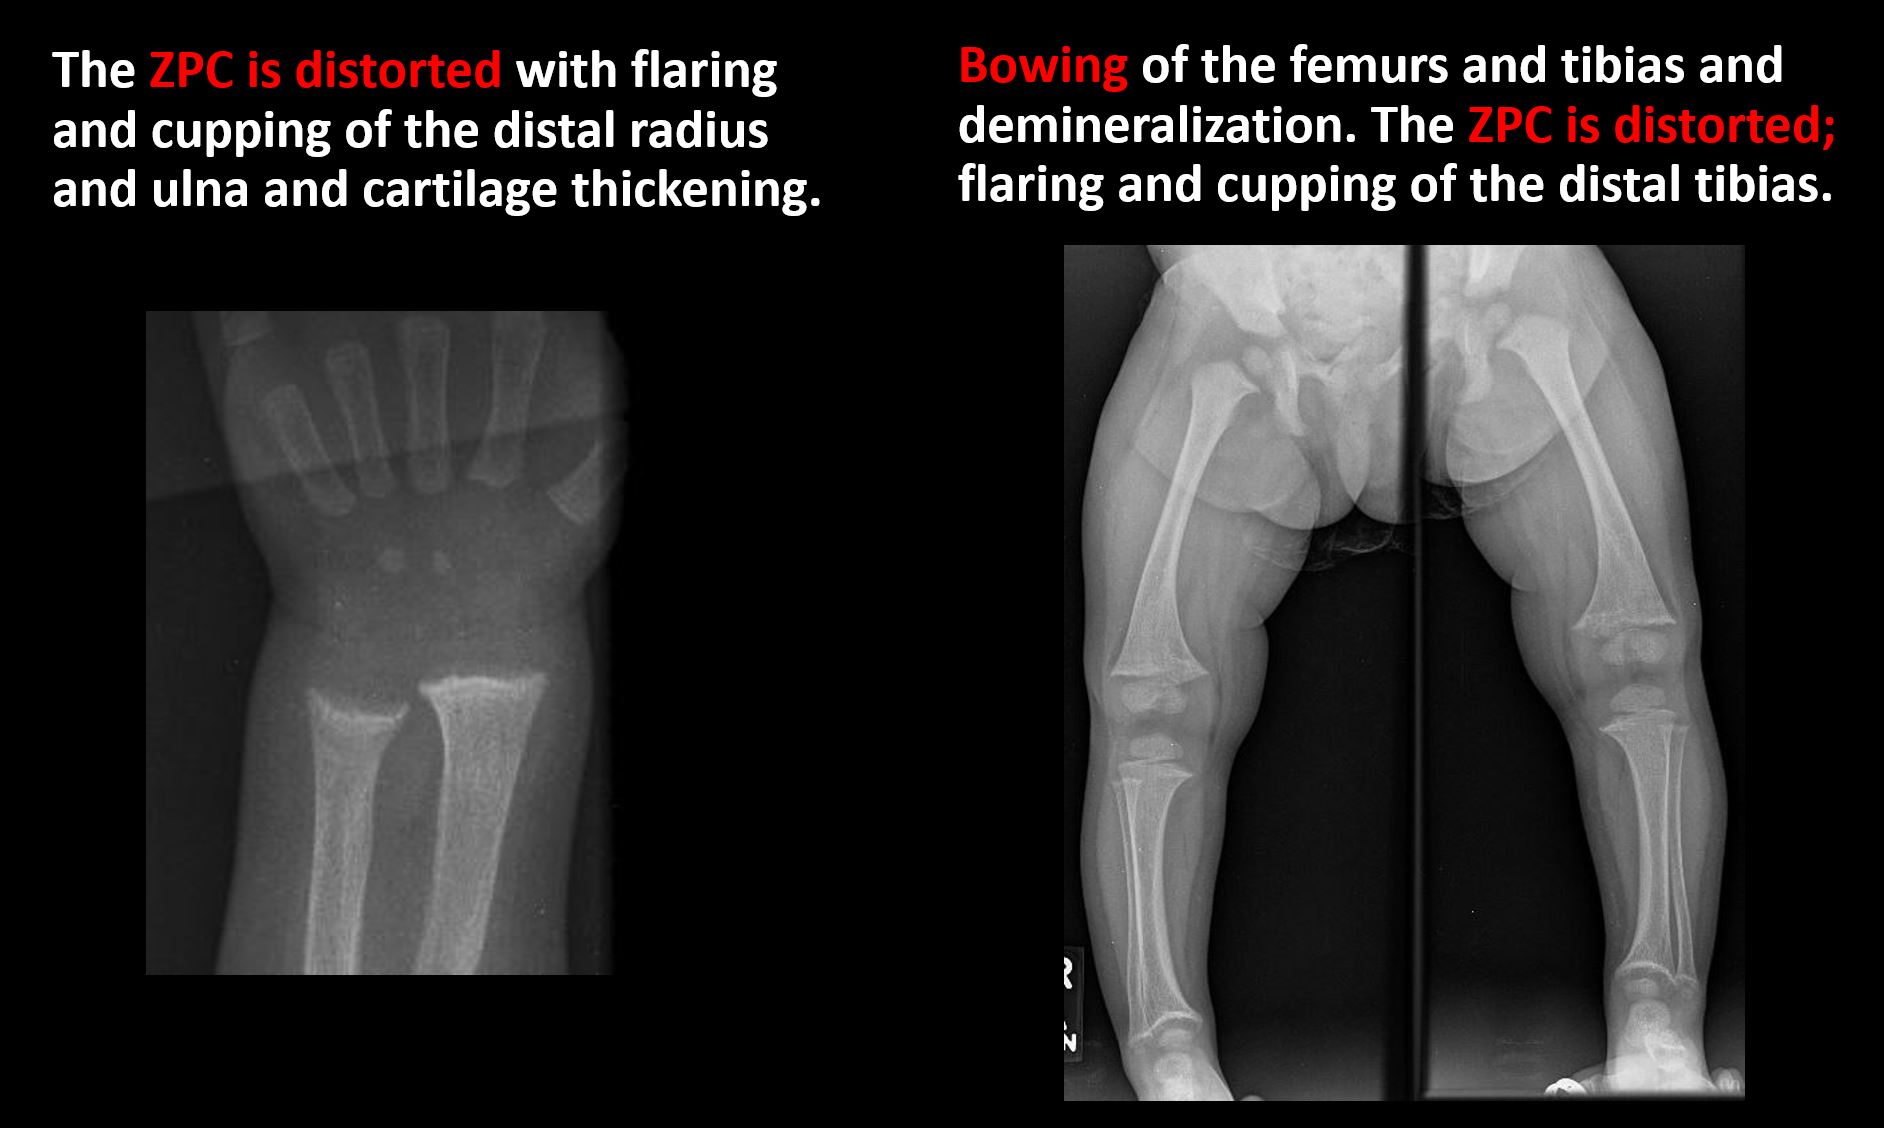

There is metaphyseal abnormality (lucencies, increased density, erosion) which may be from something other than injury such as stress, metabolic disease (e.g. rickets), neoplasm (e.g. leukemia), heavy metals, inflammation, or infection. |

No | NA |

The growth plate(s) is/are abnormal. |

Yes | NA |